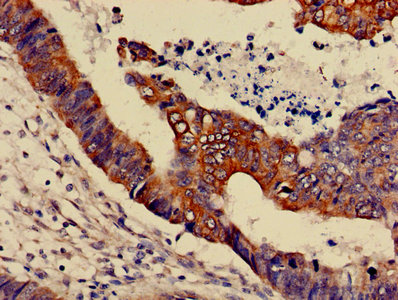

• IHC image of CSB-PA013456LA01HU diluted at 1:600 and staining in paraffin-embedded human colon cancer performed on a Leica BondTM system. After dewaxing and hydration, antigen retrieval was mediated by high pressure in a citrate buffer (pH 6.0). Section was blocked with 10% normal goat serum 30min at RT. Then primary antibody (1% BSA) was incubated at 4°C overnight. The primary is detected by a biotinylated secondary antibody and visualized using an HRP conjugated SP system.